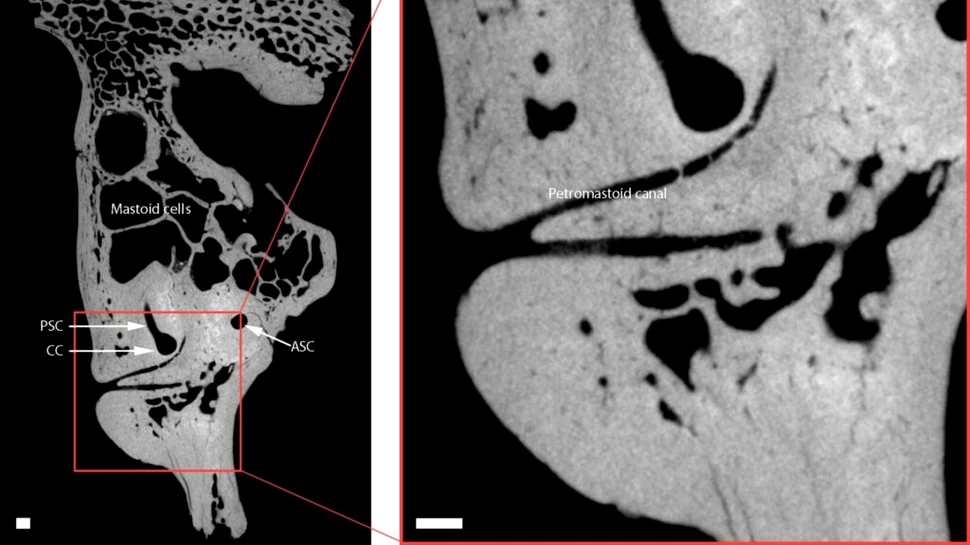

Foto: Conde-Valverde et al., Science Advances, 2024

Copiii neanderthalieni cu sindrom Down sunt reprezentați de fosila codificată CN-46700, care este un os temporal dintr-un set de rămășițe neanderthaliene excavate în 1989 de la situl din peștera Cova Negra din Spania, ocupat de specie cu între 273.000 și 146.000 de ani în urmă. Cercetătorii au folosit scanări micro CT pentru a construi un model 3D al fosilei originale pentru analiză.

Analiza a relevat că CN-46700 avea caracteristici tipice neanderthalienilor și trăsături de dezvoltare care indică faptul că copilul avea peste șase ani. De asemenea, s-au găsit semne de probleme de sănătate, inclusiv o cohlee mai mică și anomalii în cel mai scurt canal auditiv, care ar fi cauzat pierderea auzului și amețeli severe.